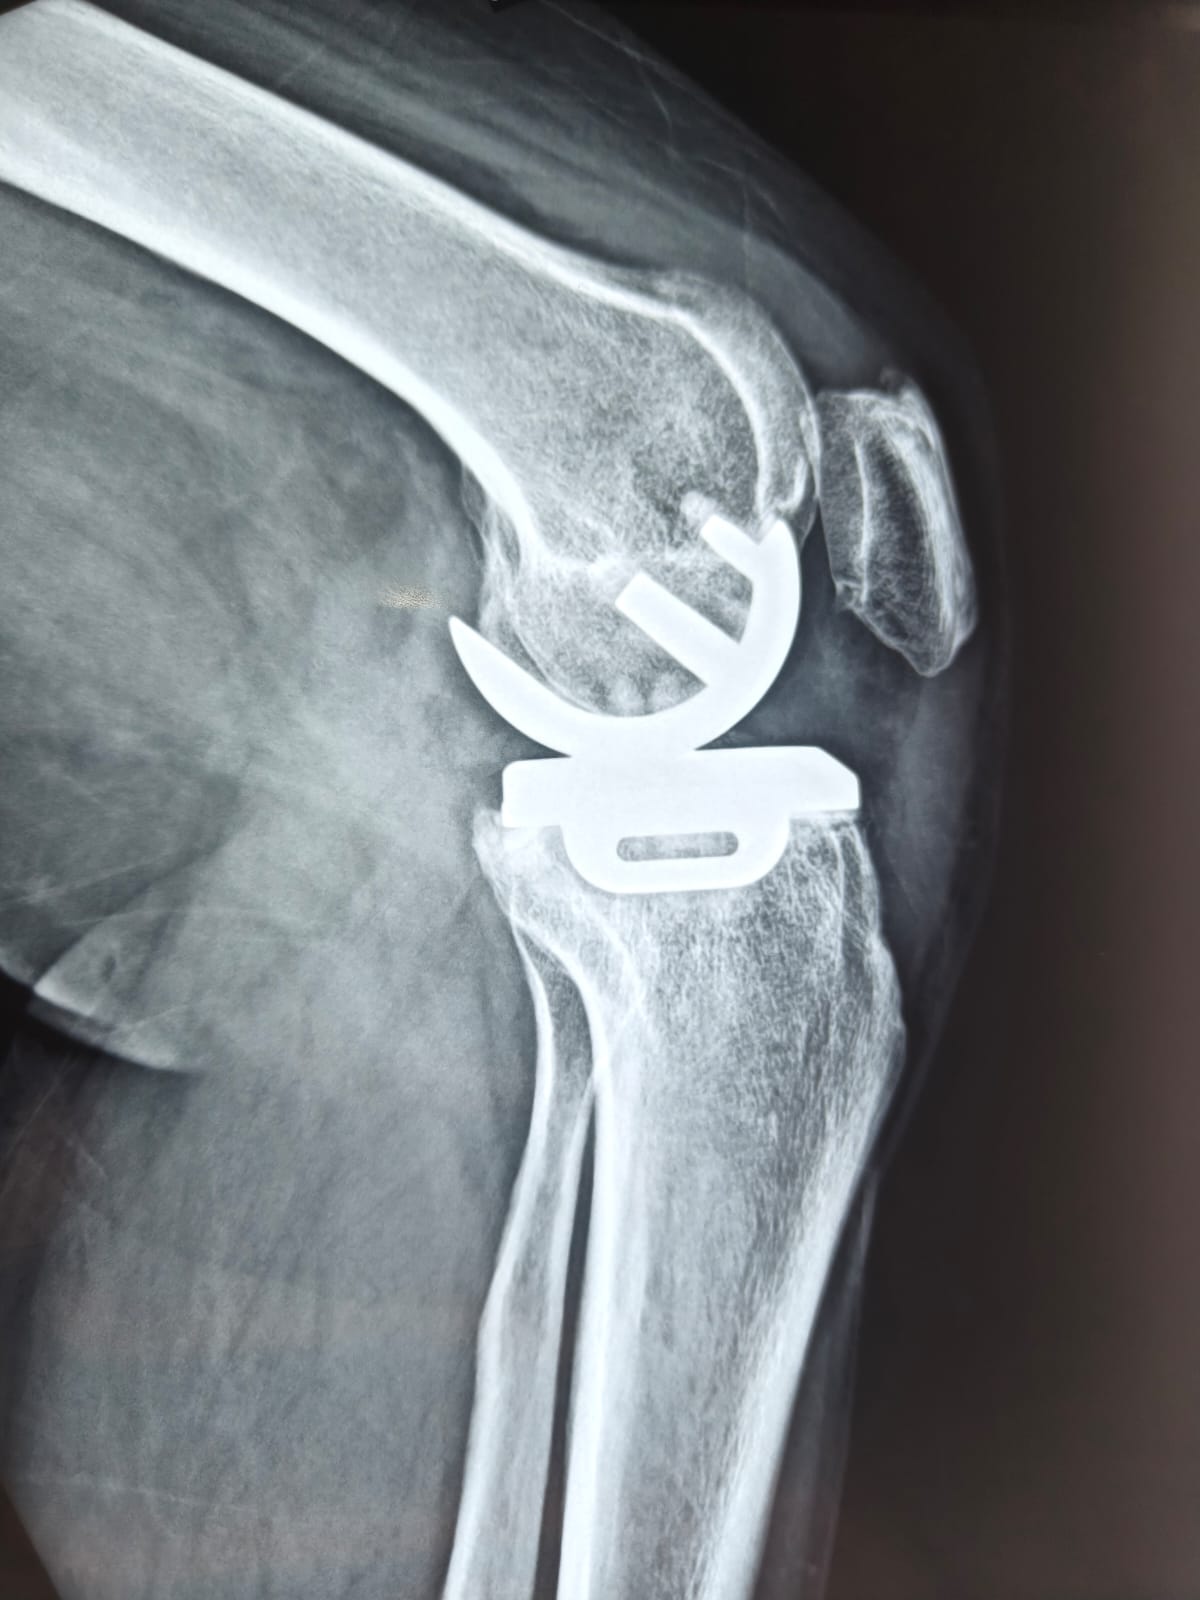

Partial knee replacement (PKR), also known as unicompartmental knee arthroplasty (UKA), is a minimally invasive surgery that helps individuals suffering from knee arthritis or injury regain mobility and reduce pain. After undergoing such surgery, one of the common questions that patients ask is whether they can return to their normal activities — specifically, whether they can sit cross-legged, a posture that is important in many cultures and daily routines.

Partial knee replacement is a procedure designed to relieve pain in the knee joint due to arthritis, fractures, or other knee conditions. Unlike total knee replacement, where the entire knee joint is replaced, partial knee replacement only addresses the damaged portion of the knee. This is ideal for patients whose arthritis is confined to a single compartment of the knee, usually the medial (inner) or lateral (outer) compartment, or the patellofemoral joint (involving the kneecap).